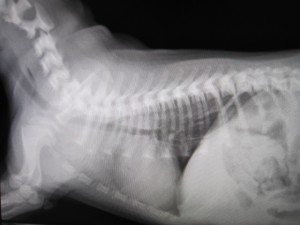

術後

術後のレントゲンです。

食道内異物はなくなりました。